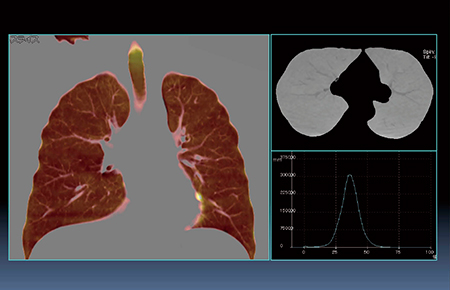

図3は,60歳,男性,非喫煙健常者のXenon画像であるが,気管内のXenon濃度が最も高く,背側の方が換気が多いことがわかる。本症例では換気はきれいな正規分布であり,これにより換気量が測定可能である。

図3 肺換気(Xenon)画像

(60歳,男性,非喫煙健常者)